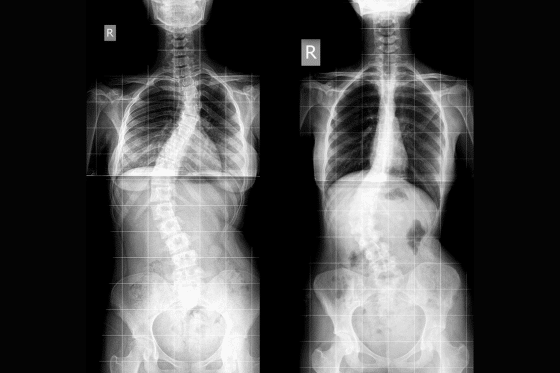

When most people think of scoliosis, they picture an X-ray with a big “S” or “C” curve and a number next to it.

In the medical world, that number is the Cobb angle. It tells us how many degrees the spine is curved when we look at it from behind.

But scoliosis is more than just a sideways curve.

A 3D Curve, Not Just a Sideways One

Scoliosis is a three-dimensional change in the spine:

• The spine bends sideways

• It also rotates, twisting the ribs and the vertebrae

• The curve can flatten or exaggerate the natural curves from front to back

That rotation is why you may notice:

• One shoulder blade sticking out more

• Ribs more prominent on one side

• A “bagel knot” or tight area along one side of your neck or low back

• Clothes hanging unevenly

It is also why two people with the same Cobb angle can look – and feel – very different. I’ve seen people with small curves and a lot of pain, and people with very large curves and almost no pain.

So if you have ever felt brushed off with, “Your curve is mild, you’ll be fine,” or scared by, “Your curve is big, there’s nothing you can do,” please know: the number alone doesn’t tell the whole story.